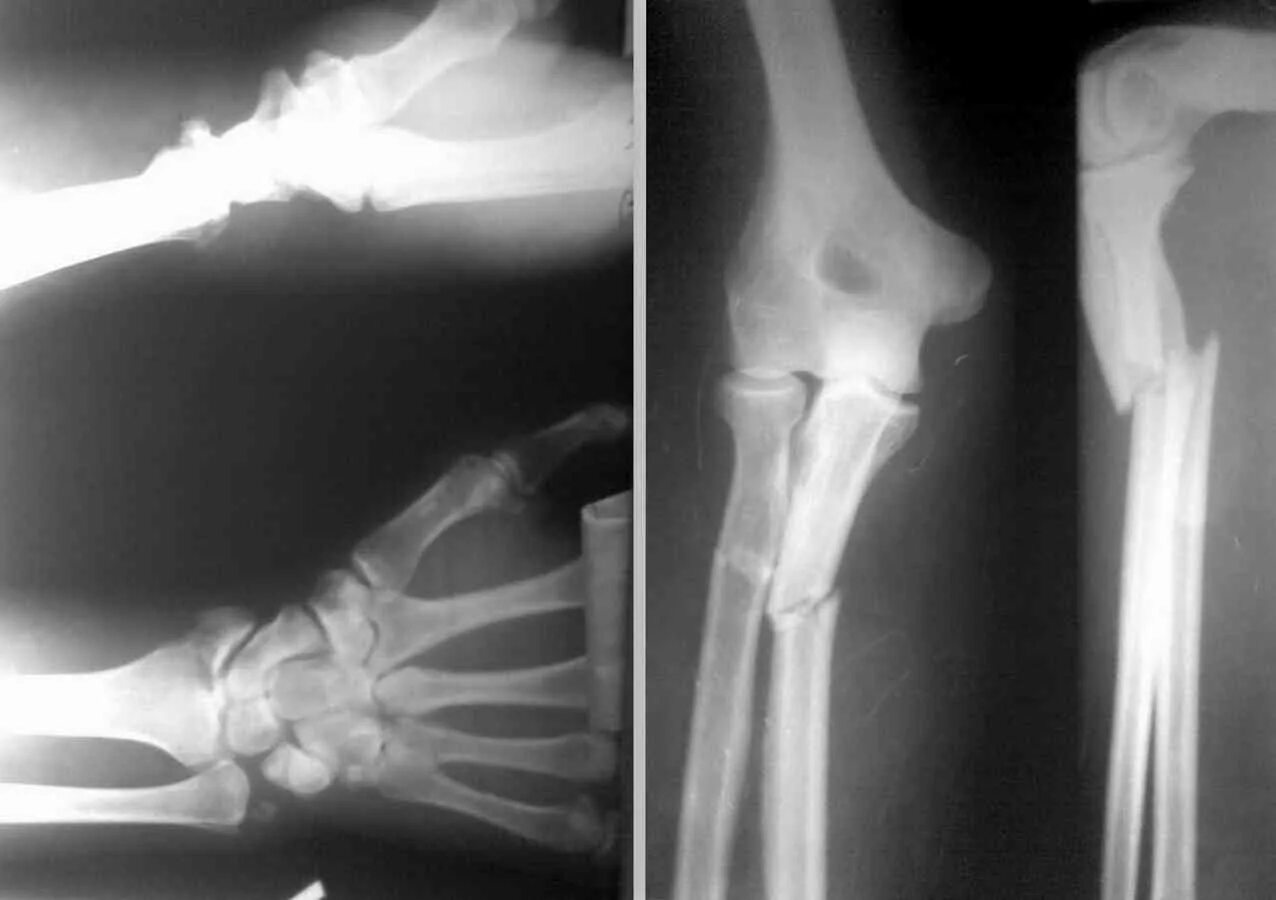

Чтоб кости быстро срослись